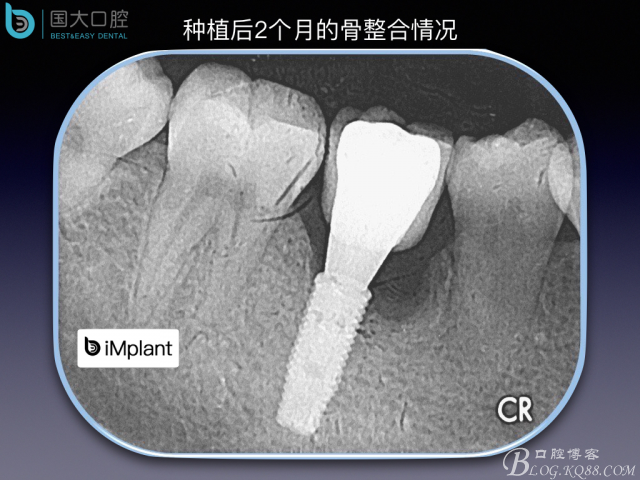

TypeC Socket即刻種植臨床案例

來源于國大口腔 邵現(xiàn)紅醫(yī)生發(fā)表的博文